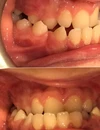

Ortodontik Malokluzyonlar

Diş Çapraşıklığı

Çarpık Diş

Ortodonti